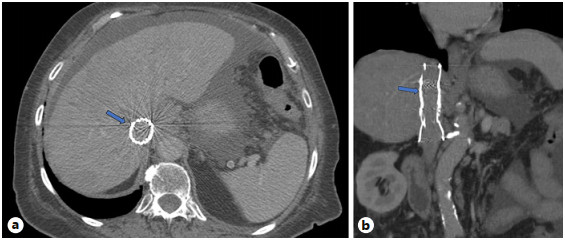

Abstract: Small bowel-origin carcinoid tumor is indolent but may metastasize relentlessly to various sites, including the liver. Over the past 9 years, we have treated a 69-year-old woman who has undergone 5 percutaneous liver ablations, 5 hepatic intra-arterial chemoembolizations, an ovarian cryoablation, and a trans-ventral hernia mesenteric cryoablation. These interventions are all related to her inoperable carcinoid malignancy. After the patient presented with swelling of the abdomen and both lower extremities, computed tomography (CT) angiography was performed, revealing a circumferential hepatic metastatic mass encasing the intrahepatic inferior vena cava (IVC) and extensive third spacing of fluids specific to the IVC distribution below the diaphragm. A venogram of the intrahepatic IVC revealed extrinsic compression causing 95% narrowing of the vessel. A balloon was advanced to the level of the lesion and inflated, increasing the caliber of the vessel. Subsequently, 2 covered aortic stent graft cuffs were deployed in an overlapping fashion within the lumen of the IVC, traversing the area of narrowing. Next, an open-cell aortic dissection stent was placed across both overlapping aortic stents from the renal veins to the hepatic veins. Following this, three 17-gauge cryoablation probes were inserted into the segment 1 intrahepatic lesions encasing the newly stented IVC via an anterior percutaneous approach. Two 10-min freeze cycles were performed with intraoperative CT imaging, demonstrating circumferential coverage of the lesions. Posttreatment venogram revealed patent stent grafts within the intrahepatic IVC, and restoration of vessel patency. No immediate postoperative complications were noted. The patient’s abdominal and lower extremity swelling resolved completely within 1 week after procedure. Two-month follow-up CT demonstrated markedly decreased size of the metastatic lesions and no adverse effects. Six- and 9-month PET-CT scans demonstrated maintained patency of the IVC stent. This palliative procedure allowed the patient to maintain good performance status and alleviated her symptoms of IVC syndrome. The radial force generated by the multiple aortic stents will ostensibly maintain the patency of the intrahepatic IVC. Cryoablation of the encasing metastatic lesion was performed with markedly decreased size of the tumor on the 2-month follow-up.